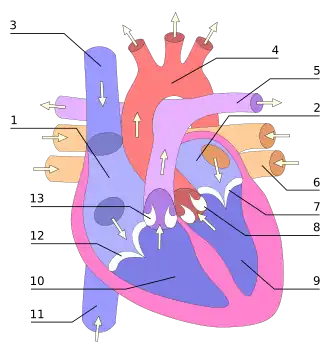

Le cœur humain est un organe musculaire creux qui assure la circulation sanguine en pompant le sang vers les vaisseaux sanguins et les cavités du corps à travers des contractions rythmiques et autonome.

- Structure et fonctionnement du cœur

Coupe frontale du ventricule gauche du cœur humain.

Coupe frontale du ventricule gauche du cœur humain. Les principales parties du cœur.

Les principales parties du cœur.- Animation d'un cœur battant.

Le cœur est un muscle creux contenant deux parties séparées bien qu'accolées l'une à l'autre : le « cœur gauche » et le « cœur droit ». Ces deux « cœurs » sont situés côte-à-côte dans l'axe base-apex, séparés par une paroi globalement verticale et orientée dans l'axe du cœur. Chacune de ces deux parties est subdivisée en deux chambres ou cavités, l'atrium (ou oreillette) vers la base et le ventricule vers l'apex. Ces deux cavités sont séparées par une valve ; on distingue ainsi la valve mitrale, entre l'atrium et le ventricule gauches, et la valve tricuspide, entre l'atrium et le ventricule droits. L'organisation est symétrique entre le cœur gauche et le cœur droit, bien que le cœur gauche soit plus volumineux. Afin que le ventricule droit puisse répondre à ses contraintes de pression dilatatrice, la trabécule septo-marginale solidarise les différentes parois ventriculaires[2].

La paroi séparant les cavités gauche et droite est appelée septum. On distingue le septum interventriculaire entre les ventricules gauche et droit, le septum interatrial entre les atriums gauche et droite, et le septum atrioventriculaire entre les atriums et les ventricules. La terminologie ne doit pas être source de confusion vis-à-vis des positions relatives ; en effet, du fait de l'axe globalement oblique vers la gauche, le cœur gauche est grossièrement situé en arrière et à gauche du cœur droit, exception faite de l'apex, principalement constitué de l'extrémité du cœur gauche.

Système valvulaire

Le système valvulaire est composé des quatre valves cardiaques séparant les différentes cavités et empêchant le sang de refluer dans le mauvais sens. Il existe la valve tricuspide, la valve aortique , la valve pulmonaire et la valve mitrale.

Circulation du sang

Le septum évite le passage direct du sang. Les valves assurent le passage unidirectionnel coordonné du sang depuis les atria vers les ventricules. Le cœur droit est dit veineux (ou segment capacitif), et le cœur gauche est dit artériel (ou segment résistif). Les parois des ventricules sont plus épaisses, et leur contraction est plus importante pour la distribution du sang contre la résistance artérielle.

Du sang appauvri en oxygène par son passage dans le corps entre dans l'atrium droit par trois veines, la veine cave supérieure (vena cava superior), la veine cave inférieure (vena cava inferior) et le sinus coronaire. Le sang passe ensuite vers le ventricule droit. Celui-ci le pompe vers les poumons par l'artère pulmonaire.

Après avoir perdu son dioxyde de carbone dans les poumons et s'y être pourvu de dioxygène, le sang passe par les veines pulmonaires vers l'oreillette gauche. De là le sang oxygéné entre dans le ventricule gauche. Celui-ci est la chambre pompante principale, ayant pour but d'envoyer le sang par l'aorte vers toutes les parties du corps.

Le ventricule gauche est bien plus massif que le droit parce qu'il doit exercer une force considérable pour forcer le sang à traverser tout le corps contre la pression corporelle, tandis que le ventricule droit ne dessert que les poumons.